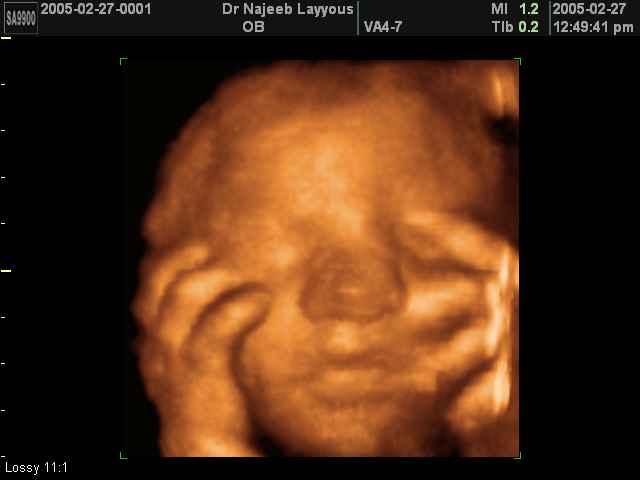

- Fetal Face Ultrasound Photos